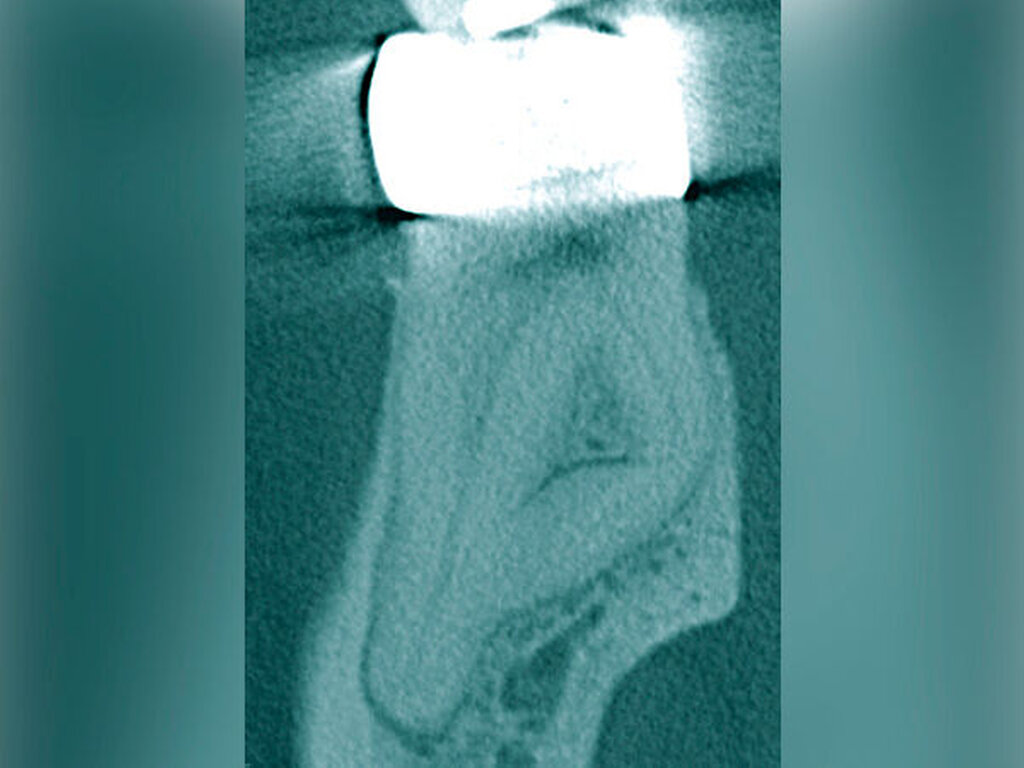

Auf der intraoralen Röntgenaufnahme lagen eine unvollständige Wurzelkanalfüllung und eine apikale Aufhellung am Zahn 45 vor. Apikal ist auf der Röntgenaufnahme kein Wurzelkanal erkennbar. Die zu kurze Wurzelkanalfüllung deutete auf eine apikale Blockade von eingepresstem Debris oder eine Stufenpräparation hin (Abbildung 14). Als seltene anatomische Variation war eine apikale Aufteilung in zwei Wurzelkanäle in Betracht zu ziehen, so dass die Nutzung einer optischen Vergrößerung mit koaxialer Lichtzufuhr als Hilfsmittel empfehlenswert erschien. Die apikale Wurzelkrümmung ließ einen gleichmäßigen großen Krümmungsradius vermuten. Bei lateralen Aufhellungen ist mit einem lateralen Foramen apicale oder einer Wurzelkanalaufteilung zu rechnen, so dass in diesem Fall die apikale Erweiterung und der Verschluss eine sehr hohe Schwierigkeit vermuten lassen.

Die Differenzialdiagnostik und die Therapie unterlagen erwartungsgemäß dem sehr hohen Schwierigkeitsgrad. Es wurde eine dentinadhäsive Aufbaufüllung mit Restauration des fehlenden Kontaktpunkts bei subgingivaler Lage des Füllungsrandes erforderlich und zusätzlich musste die apikale Blockade minimalinvasiv mit modernen endodontischen Hilfsmitteln eliminiert werden. Die Entfernung der alten Wurzelkanalfüllung gelang in der Kombination von Handinstrumenten und rotierenden NiTi-Feilen (Abbildungen 15a und 15b). Unter Sicht mit dem Dentalmikroskop konnte die intrakanaläre Blockade mit Ultraschall und vorgebogenen Feilen überwunden und thermoplastisch verschlossen werden, so dass bereits sechs Monate nach Therapieabschluss die apikale Aufhellung und klinische Schmerzsymptomatik abgeklungen waren (Abbildung 15c).